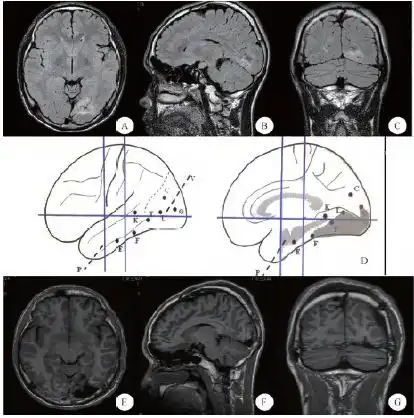

a(轴位),b(矢状位),c(冠状位):术前mri,显示围距状裂异常信号,考虑为